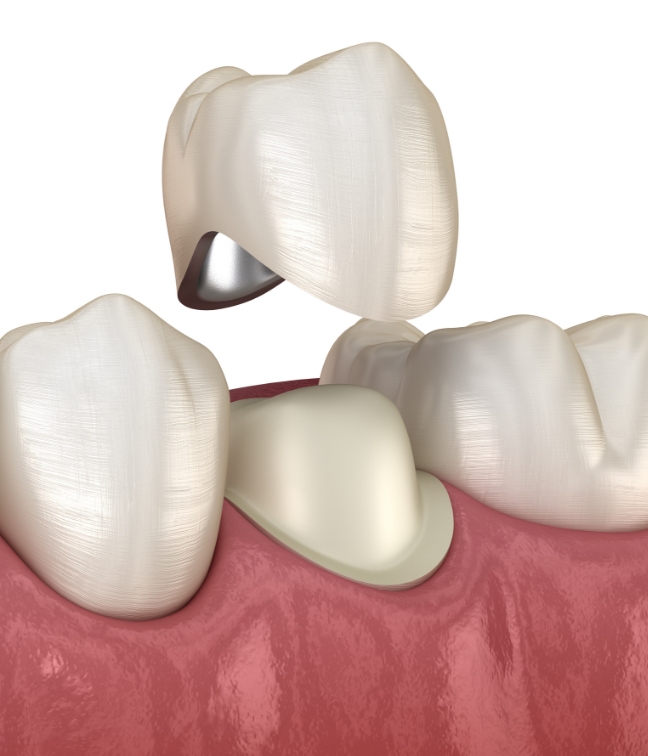

在进行根管治疗后, 为保护已变脆弱的牙齿,

通过整体包覆的方式进行修复,

是一种能同时恢复

受损牙齿功能的治疗,

并改善牙齿的美观效果